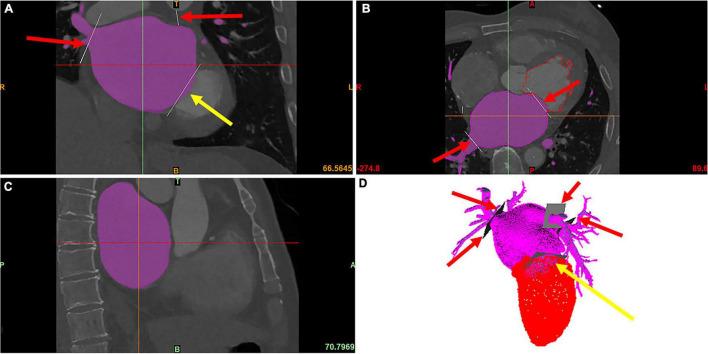

Cardiac CT images were obtained from AF patients with ( = 10) and without a history of stroke ( = 10). 3D models of the left atrium (LA) were reconstructed by processing the CT image, and the LA/LAA morphological parameters were measured. Computational fluid dynamics (CFD) simulations were performed to calculate the hemodynamic parameters in LA. The species-transport model and discrete phase model (DPM) were applied to analyze blood residual ratio and particle residual ratio, two qualitative parameters for thrombus formation and flow-out potential, respectively.